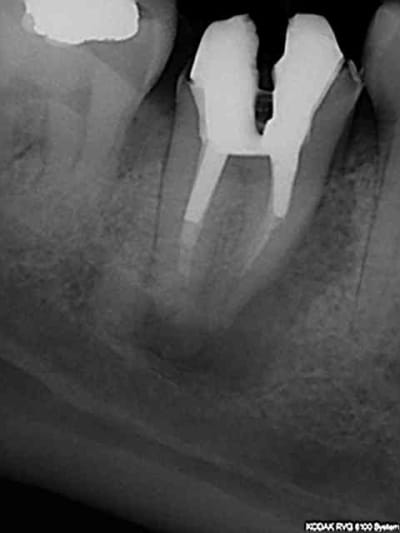

> @Chicot29: Tes endos sont superbes. Ce type de travail n'a aucune valeur pour

> santeclair et les autres guignols. Il n'y a que le prix, le prix, le prix. Tout

> le discours sur la qualité et le respect des normes de bonne pratique est de

> l'enfumage. Le but c'est de baisser le prix UN POINT C'EST TOUT. Il y a un

Ca c'était le cas de 14 h, voici le cas de 11h plus délicat. On verra ce que ca donne dans le temps ( finition au R40). C'est un peu creux en ce moment, heureusement qu'il y a des traitements réalisés conformément aux données acquises de la science à reprendre !)))))